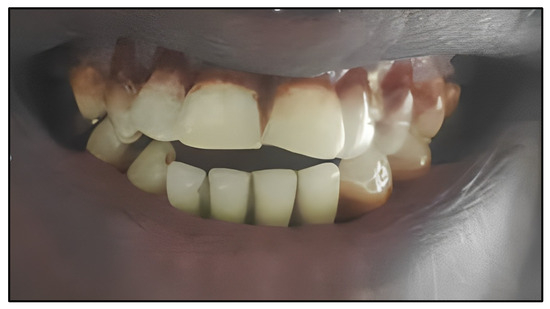

3.1. Teeth Characterization